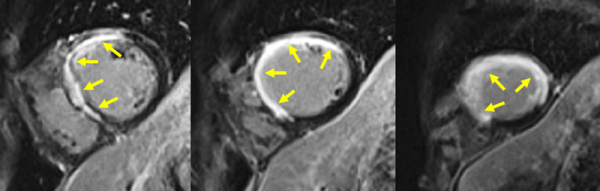

Figure 2A : Séquence de perfusion premier-passage au repos - Coupes petit-axe médian

Figure 2B : Séquence de perfusion premier-passage au repos - Coupes 2-cavités

Figure 2C : Séquence de perfusion premier-passage au repos - Coupes 4-cavités

Présence d’une hypoperfusion sous-endocardique de toute la paroi antéro-septo-apicale débordant sur la paroi apico-latérale. Cette hypoperfusion correspond à la zone de l’infarctus.

Aucun thrombus intra-VG n’est visualisé sur ces séquences de perfusion de premier passage de repos. En effet, un thrombus serait apparu sous la forme d’une masse apicale en hyposignal (noire) avec un produit de contraste qui aurait moulé le thrombus.